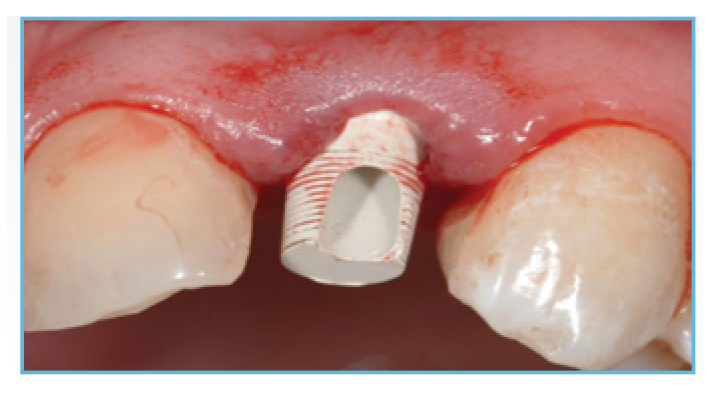

Fig. 2. A PreFormance Post was seated into the implant.